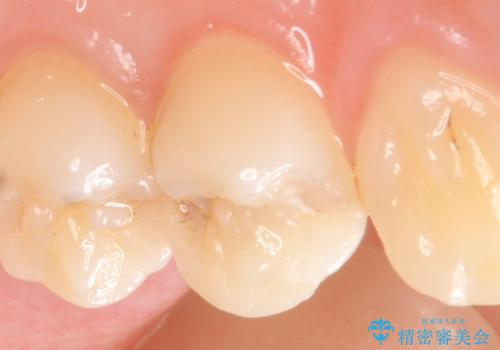

セラミックインレー 虫歯で欠けた歯の治療

- 左上4番目の歯が欠けてしまったので診て欲しいといらっしゃった方の症例です。

白い詰め物を御希望されたので、セラミックインレーによる修復を行いました。